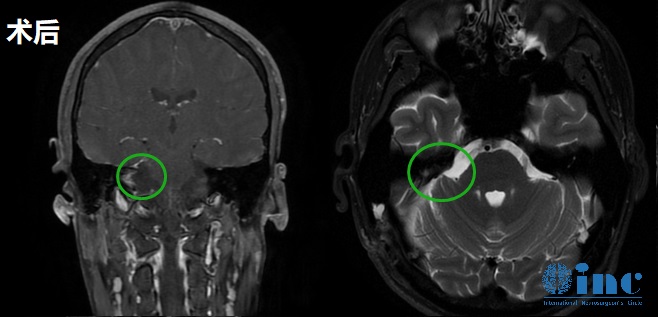

手術(shù)在術(shù)中神經(jīng)電生理監(jiān)測下順利進行,巴教授采取半坐位手術(shù)體位通過右乙狀竇后入路折骨開顱術(shù),在保護面神經(jīng)完整性下, 進行腫瘤顯微外科切除術(shù),順利全切嘉宇巨大的聽神經(jīng)瘤,術(shù)后無新發(fā)神經(jīng)損傷。

聽神經(jīng)瘤術(shù)后影像

術(shù)后二天嘉宇回到普通病房,可自行喝水,吞咽正常,無嗆咳,可自行就餐。